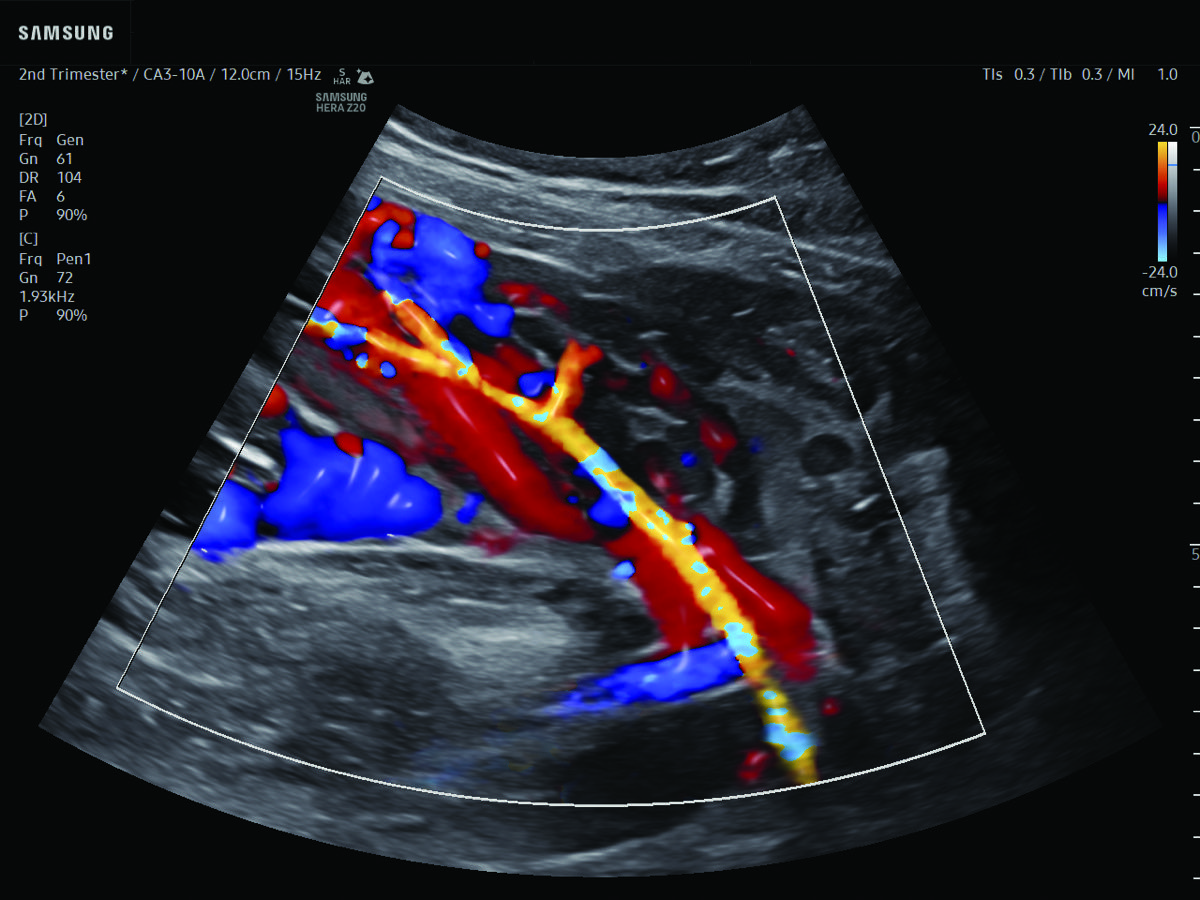

Procedural Services

Comprehensive, advanced and expert MFM care for high-risk pregnancies

- Fetal anomalies